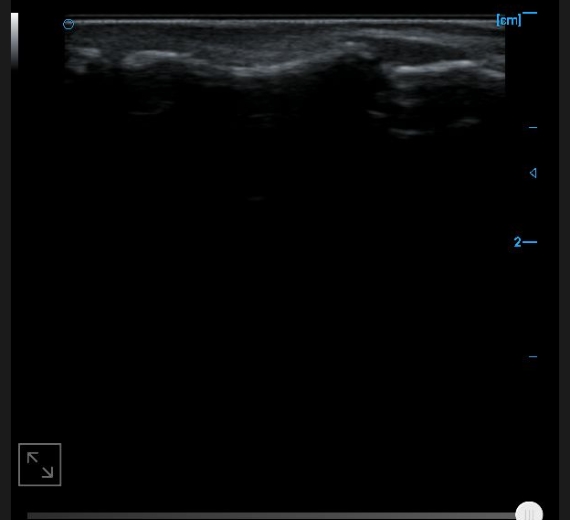

Patellar tendon B image

B-image of quadriceps tendon

Knee collateral ligament B image

B-image of femoral trochlear cartilage